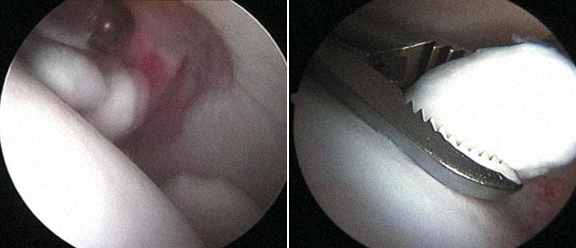

4 - Quisto intra-articular - exérese